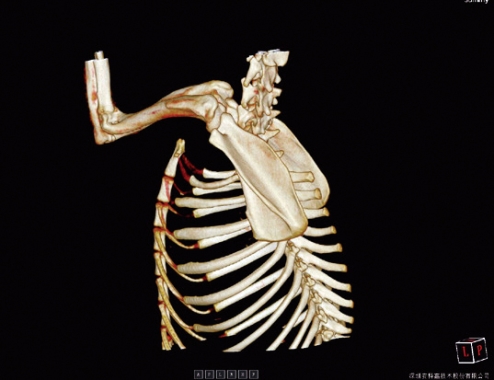

APLICAÇÕES CLINICAS